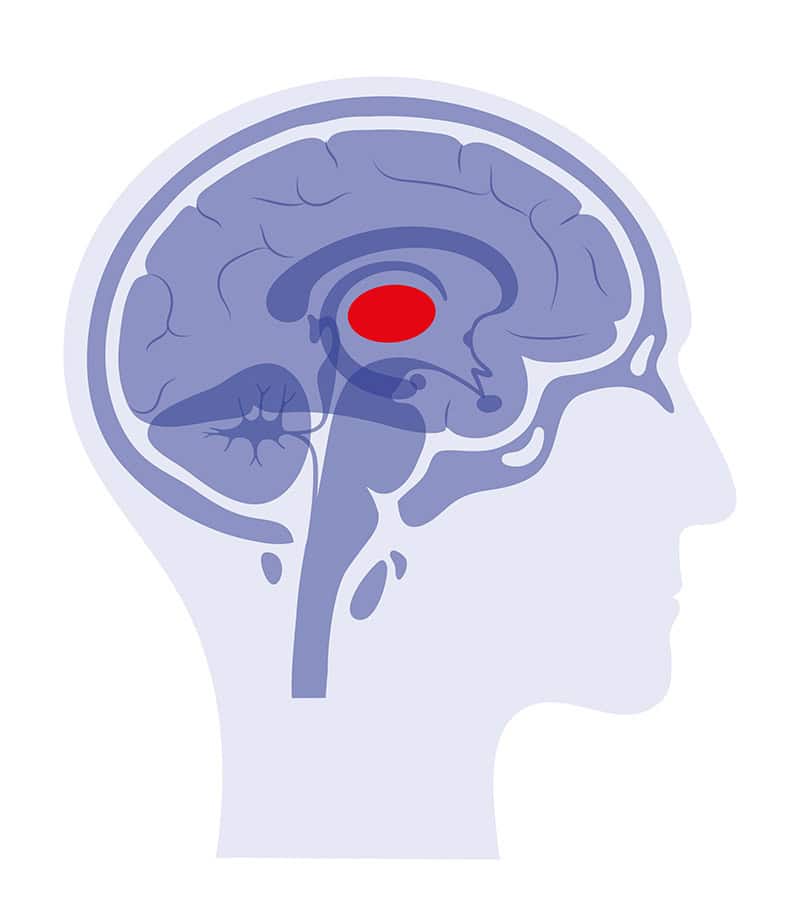

Metastatic Brain Tumors

Metastatic brain tumors are cancers that spread to the brain from another part of the body, most commonly the lung, breast, kidney, or skin. These are the most common brain tumors in adults. They can be single or multiple and may grow at different speeds depending on the primary cancer. Because these tumors can develop quickly, early evaluation and coordinated treatment are essential.